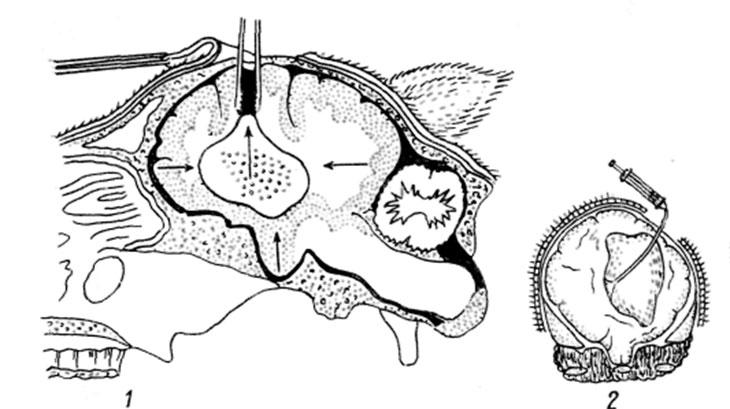

Die Krankheit wird hauptsächlich operativ behandelt - durch Trepanation des Schädels wird Flüssigkeit aus der Blase abgesaugt und die Membran vorsichtig entfernt. Auf diese Weise werden Individuen wertvoller Rassen gerettet.

Eine Alternative zur Operation ist die Zerstörung von Parasiten mit den Medikamenten Praziquantel, Niclosamide, Albendazol. Nach der Chemotherapie müssen Glukokortikoidmittel verwendet werden, um entzündliche Prozesse zu unterdrücken. Wenn die Behandlung der Coenurose im Anfangsstadium (im Stadium der Larvenmigration) begonnen wird, werden Injektionen mit den Arzneimitteln "Febendazol", "Praziquantel" verwendet. Den Tieren werden Medikamente in den gewünschten Bereichen des Kopfes verabreicht.